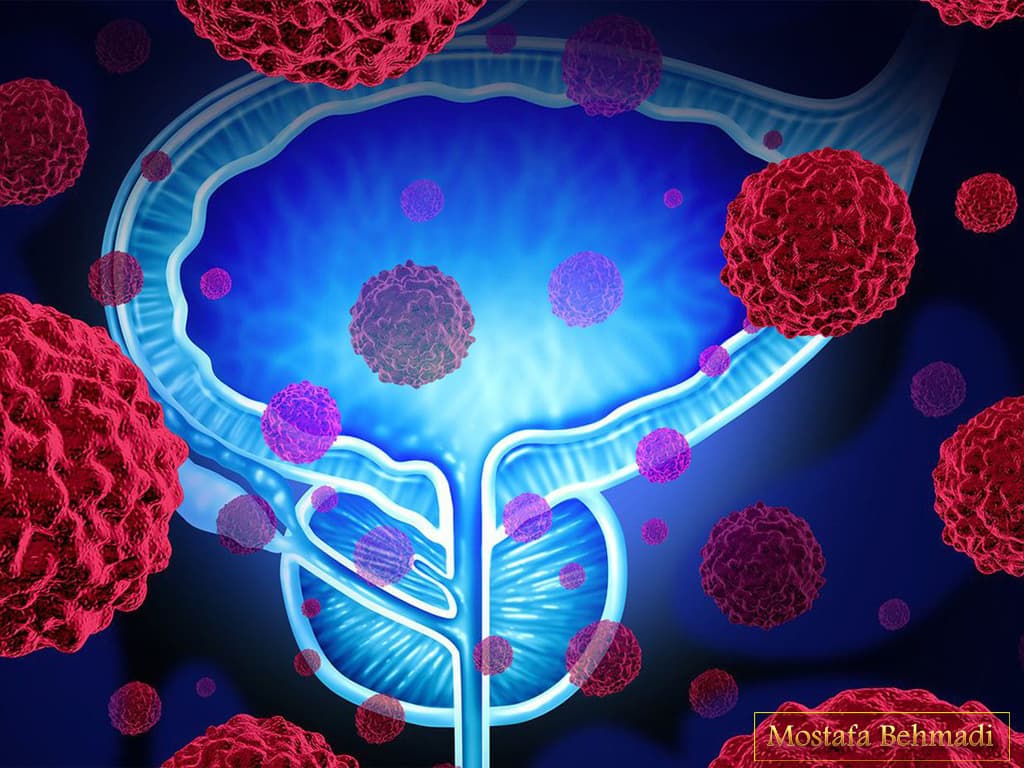

مراحل سرطان پروستات

درجه بندی کنسر پروستات به میزان شباهت سلول ها ی پروستات به سلول های طبیعی و سرطانی بستگی دارد.یعنی هر چه سلول مورد مطالعه از سلول های طبیعی از نظر عملکرد و ساختار تفاوت داشته باشد درجه ی سرطان بالاتر گزارش می شود .این درجه بندی در یک معیار از ۲ تا ۱۰ قرار داد شده است و در معیار دیگری به نام گلیسون از ۱ تا ۴ درجه بندی شده است.هر چه درجه سرطان بالاتر باشد،میزان رشد و گسترده شدن و انتشار در بدن نیز افزایش می یابد.در مرحله یک و دو ،سرطان پروستات به صورت موضعی رشد کرده و از محل خود فراتر نرفته است. در مرحله ۳ که به آن موضعی پیشرفته گفته می شود ،سلول های سرطانی به کیسه ی منی نیز منتشر می شوند و در مرحله ی چهار ،سلول ها توسط خون و لنف به سایر قسمت های بدن نیز نفوذ پیدا می کنند.